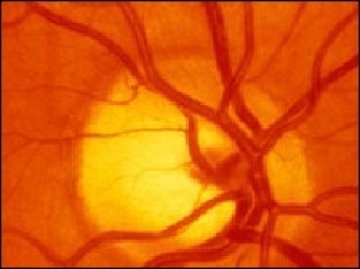

Група британски учени успяха да върнат зрението на слепи мишки като имплантираха стволови клетки, съобщава BBC. Този експеримент е твърде вероятно да открие пътя към лечение на хора, загубили възможността си да виждат света.

По време на изследването, чиито резултати са публикувани в списание Nature, стволовите клетки са били присадени в очите на мишки, загубили зрението си заради генетична болест, аналогична на тази, която довежда до слепота при хората.

За разлика от предишни експерименти, учените са използвали не зародиши на стволови клетки, а клетки, които вече са се развили.

„Успяхме да докажем, че присаждането на фоторецептори е възможно – каза британският учен Робърт Макларън, един от авторите на изследването. - Тези клетки умират от някои от най-разпространените болести, предизвикващи слепота“.

По-рано всички опити за присаждане на зародишни стволови клетки в очи са били неуспешни, защото тези клетки не са се развивали във фоторецептори.